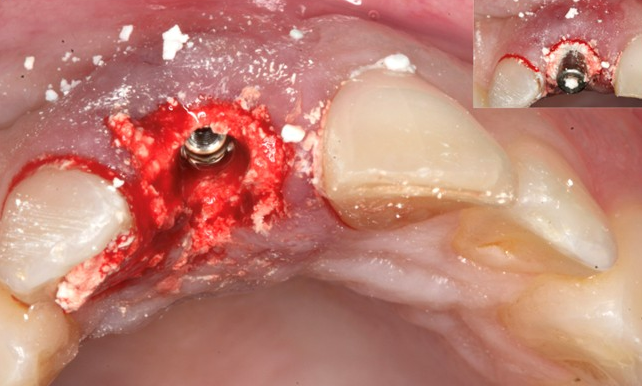

2. Immediate Implant Placement with Flap Reflection

Step-by-Step Protocols for Immediate Implant Placement with Flap Reflection

- Elevate a gingival flap according to the Augma protocol (Socket Grafting with Flap Reflection).

- Drill the osteotomy, insert the implant, and confirm good primary stability in the bone.

- Activate the Bond Apatite® syringe and inject the material from the bucco-occlusal direction with slight overfill.

- Compact the material immediately by pressing a dry, sterile gauze pad simultaneously from the occlusal and buccal sides for about 3 seconds. Then compact again with a periosteal elevator over the gauze for 3–4 seconds.

- Reposition the gingival flap as is, without trying to gain tension free flap by periosteal releasing incisions Do not attempt primary closure.

- Suture the flap papilla-to-papilla, then suture the vertical incision area. Primary closure is not required.

- Protect the exposed material with Augma Shield™, secured and sutured tightly over the gums according to the protocol, to prevent washout during healing.